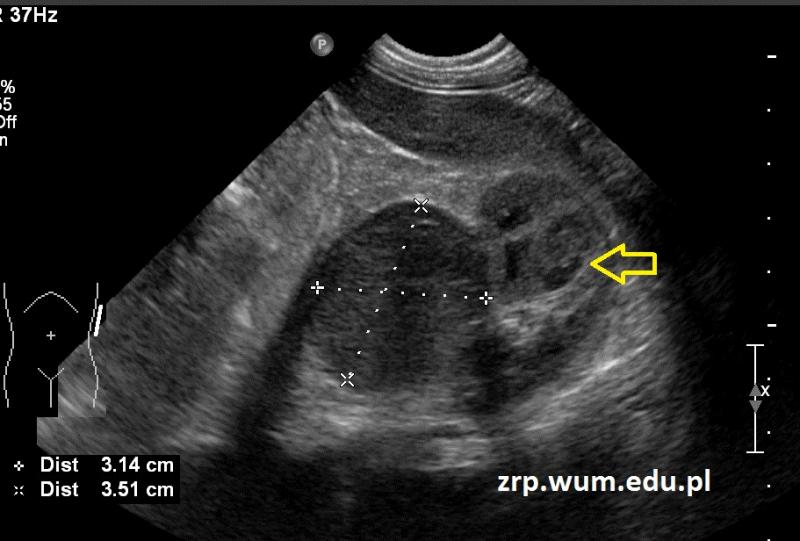

Rozpoznanie: W badaniu USG uwidoczniono owalną hipoechogenną dobrze odgraniczoną zmianę (35x31mm), zlokalizowaną przyśrodkowo od górnego bieguna nerki lewej (żółta strzałka). W toku dalszej diagnostyki rozpoznano raka kory nadnercza.